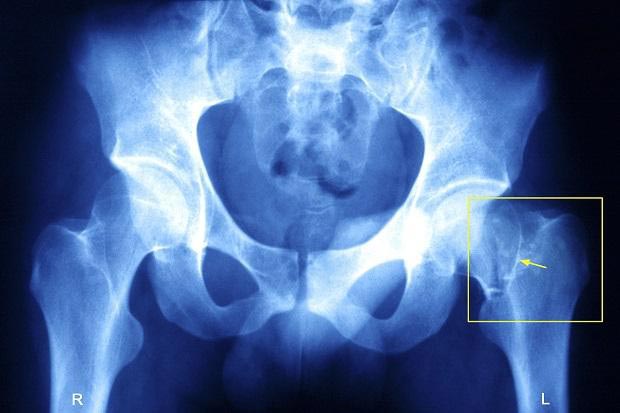

استخوانبندی بدن خود را شکننده میکنید.

تا سن ۳۰ سالگی، سرعت استخوانسازی بدن بیشتر از تجزیهی استخوانی است. پس از ۳۰ سالگی، تجزیه استخوانها از ساخت آنها سبقت میگیرد. بهترین روش برای تقویت اسکلت بدن؟ کلسیم.

به گفتهی دکتر ربکا بلک، مدیر مرکز تغذیه بالینی در نیویورک لبنیات یکی از بهترین منابع تامین کلسیم است، زیرا بدن کلسیم موجود در لبنیات را، در مقایسه با دیگر غذاها، بهتر جذب میکند. با حذف لبنیات گامی در جهت پوکی استخوان و شکستگی آنها برمیدارید.

او در ادامه میافزاید که اگر شما قصد حذف شیر گاو را از برنامهی غذایی خود دارید، سایر منابع کلسیم برای تقویت اسکلت بدن همچون سبزیهای برگدار (چغندر،کلم پیچ، اسفناج، بروکلی ) توفو و ساردینها را بیشتر مصرف کنید.

همچنین، به گفتهی بلک، روزانه یک مکمل کلسیم و یک مکمل ویتامین D بخورید. قطعا آنها را به همراه غذا مصرف کنید، زیرا اسید معده به جذب آنها کمک میکند.